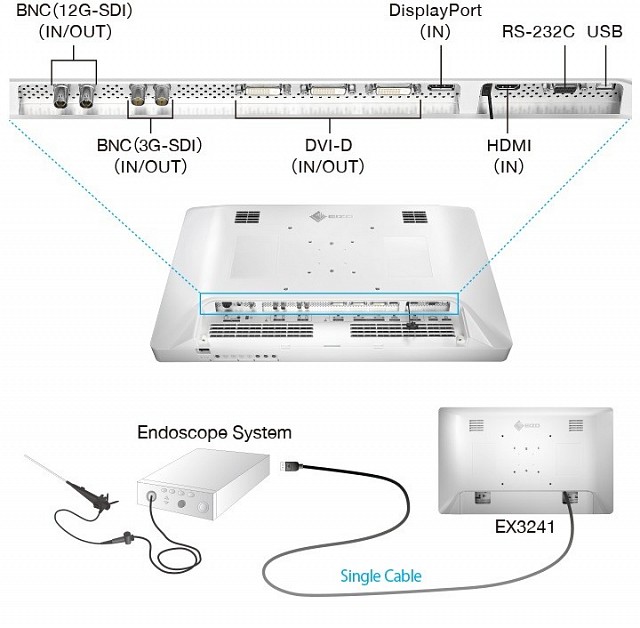

- DisplayPort 1.2、12G-SDI和HDMI,可轻松连接

- 12G-SDI(BNC)用于长距离连接

使用附带的电缆盖,可以将电缆整齐地存放在视线之外,从而提高手术室的安全性和卫生性。